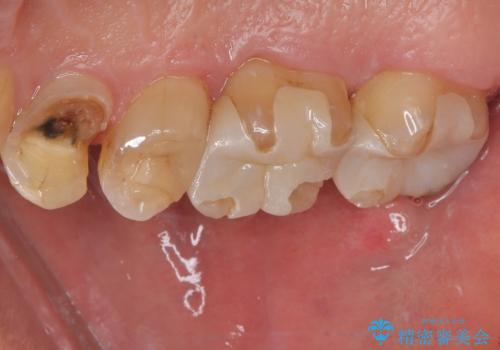

- 食事中に歯が欠けてしまった事を主訴に来院された患者様です。

小臼歯が広範囲に欠けてしまっています。

部分的な詰め物では再びかけてしまうリスクが高いため、オールセラミッククランにて補綴治療をすることとしました。